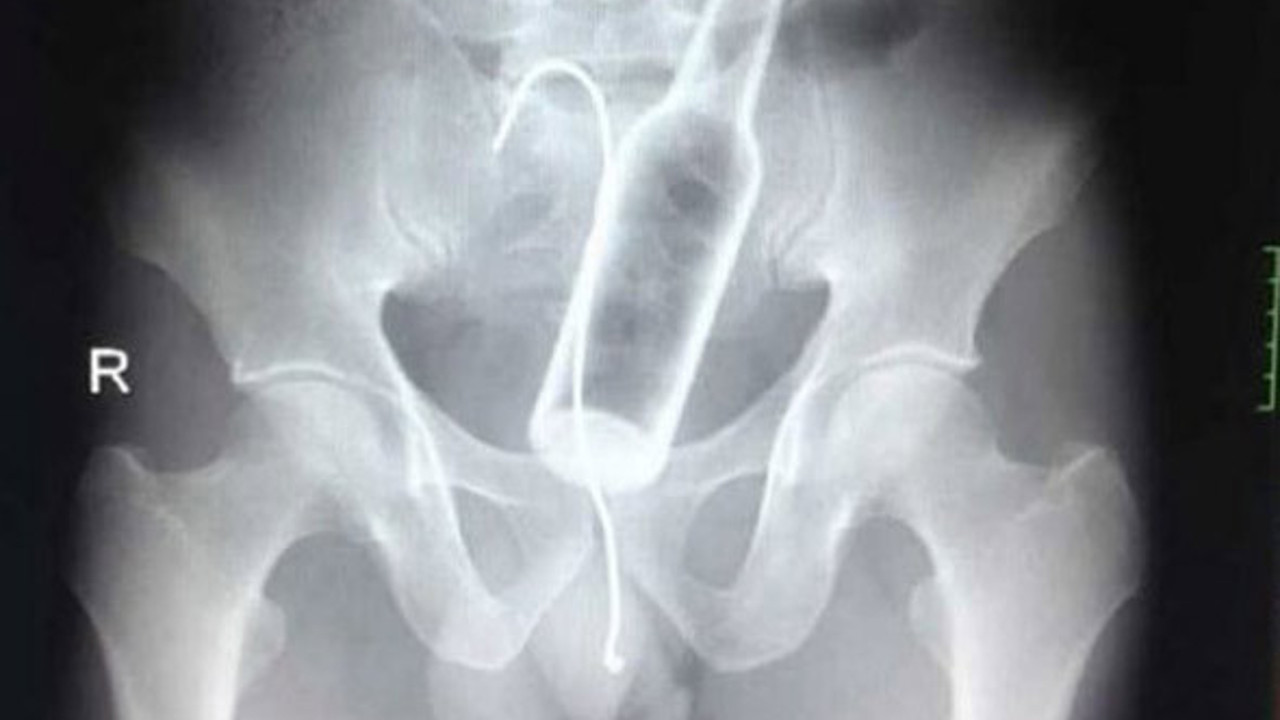

Bir röntgen sonucu neler gösterebilir? Sandığınızdan daha çok şey. Dünyanın dört bir yanından gelen röntgen görüntüleri, görenlerin ağzını açık bırakacak cinsten. Midesinden yasaklı madde çıkan mı dersiniz yoksa ayakkabı mı? Bunlar yapışık ikizlerin röntgeni. Daha ilginçleri ise sizi galerinin devamında bekliyor. İşte birbirinden ilginç ve şaşırtıcı röntgen sonuçları... Hamile bir kedi ve onun röntgen filmi. Hamile bir kaplumbağanın röntgen filmi. Yemek yedikten hemen sonra röntgen filmi çekilen yılan. Doktorların çektiği röntgen sonucu görüntülenen midedeki şişe. 13 aylık bir bebeğin yuttuğu piller. Hollanda'da 52 yaşında bir kadın 78 tane gümüş kaşık yuttu. Çengelli iğne. Kaçakçılık yapmak için yutulan uyuşturucular.